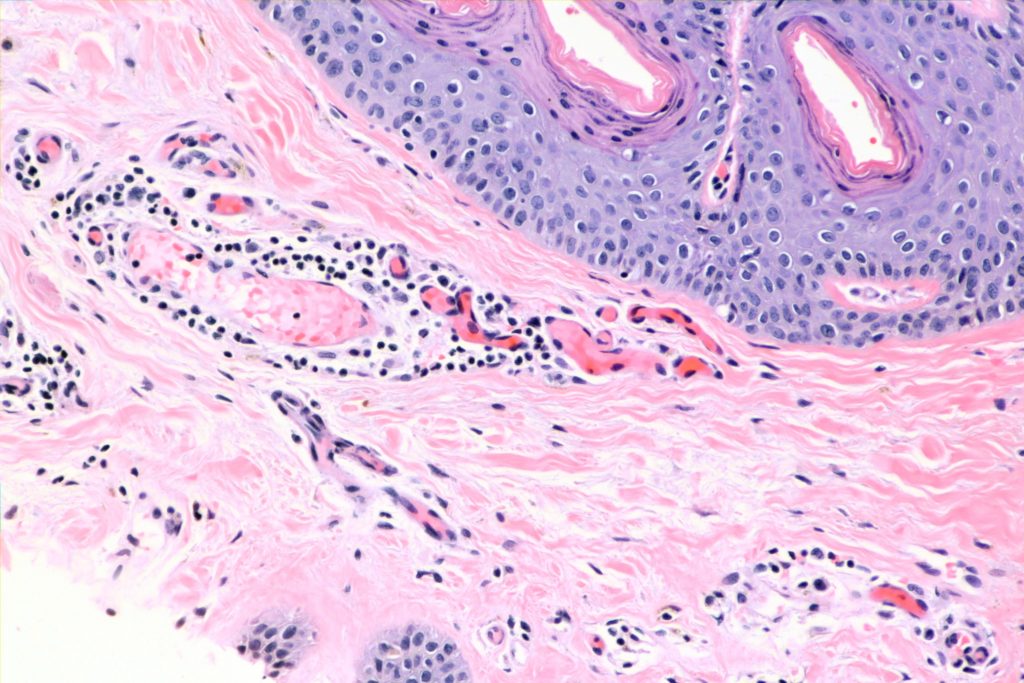

Histologically, the keratinizing epithelium is intact, but there is a vasculitis with perivascular extravasation of erythrocytes:

It’s a decent idea, but you’ll note that the epidermis itself looks pretty good in my case. The key difference is that this is a vasculitis with no damage to the epithelium — the erythema is due to perivascular extravasation. I suspect that if it was due to picking at yourself, you’d see ulcerations.